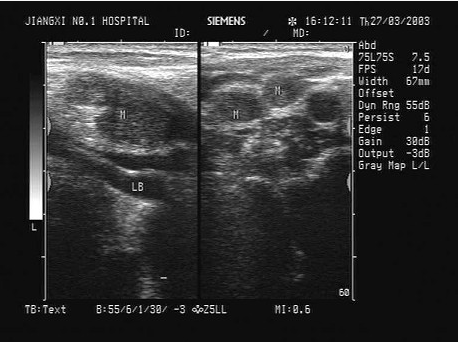

临床资料:男,50岁,自述胃癌术后3年余。超声综合描述:右锁骨上窝扫查可见数个长圆形低回声区,最大1.7cm×1.1cm,边界尚清,内回声欠均匀,部分互相融合,CDFI:内可见少许动脉血流信号。见下图及彩图。

超声提示()。

A.右锁骨上窝淋巴结结核

B.右锁骨上窝囊肿

C.右锁骨上窝肿大淋巴结(淋巴结转移瘤)

D.右锁骨上窝正常淋巴结声像图